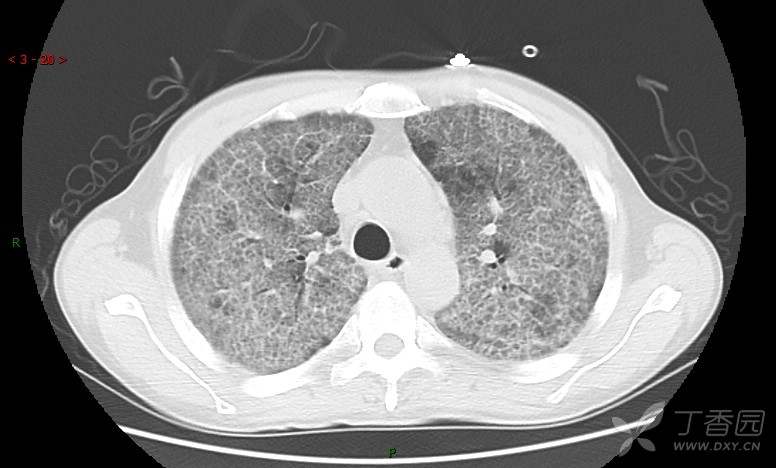

地图+铺路石征=PAP?那升高的CEA怎么说(病例3连发,附其他2例链接)

患者男,42岁,咳嗽半年余,加重伴憋喘2月余。

患者半年余前无明显诱因出现间断咳嗽,干咳为主,偶咳少量黄白痰,剧烈咳嗽或运动后可出现轻度憋喘,无高热、脓臭痰,无胸痛、咯血及晕厥,无低热乏力及盗汗,无心前区压榨感及夜间阵发性呼吸困难,初未在意,未予正规诊治。2月余前患者自觉上述症状较前加重,咳嗽、憋喘明显,黄白色粘痰略有增多,伴有发热,热前伴有畏寒、寒战,体温最高达38.9℃,先后就诊多家医院,入住重症监护室,未行气管插管,考虑“重症肺炎”,给予“美罗培南、复方磺胺甲噁唑”等药物抗感染,“卡泊芬净”抗真菌,并给予“甲泼尼龙”等药物治疗35天,经治疗后症状好转于2018-04-02出院。患者自出院后仅应用中药治疗(具体不详),并给予家庭氧疗,平素仍有间断咳嗽,咳少量黄白色粘痰,活动后憋喘明显,活动耐量差,以卧床为主。

肺内弥漫性网状结节影,PET-CT却无阳性病灶,这是?(附其他2例链接)